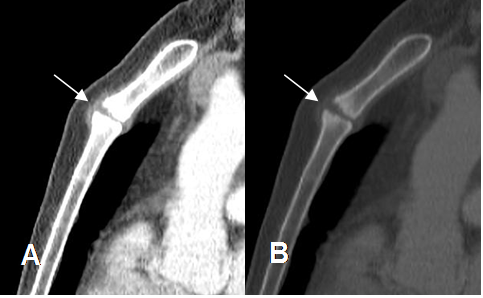

Fig 32. Cambios degenerativos.

A: TAC reconstrucción sagital en ventana de tejido y B: en ventana de hueso. Esclerosis en los bordes sobre el ángulo de Louis, con prominencia de los tejidos blandos, por proceso degenerativo.